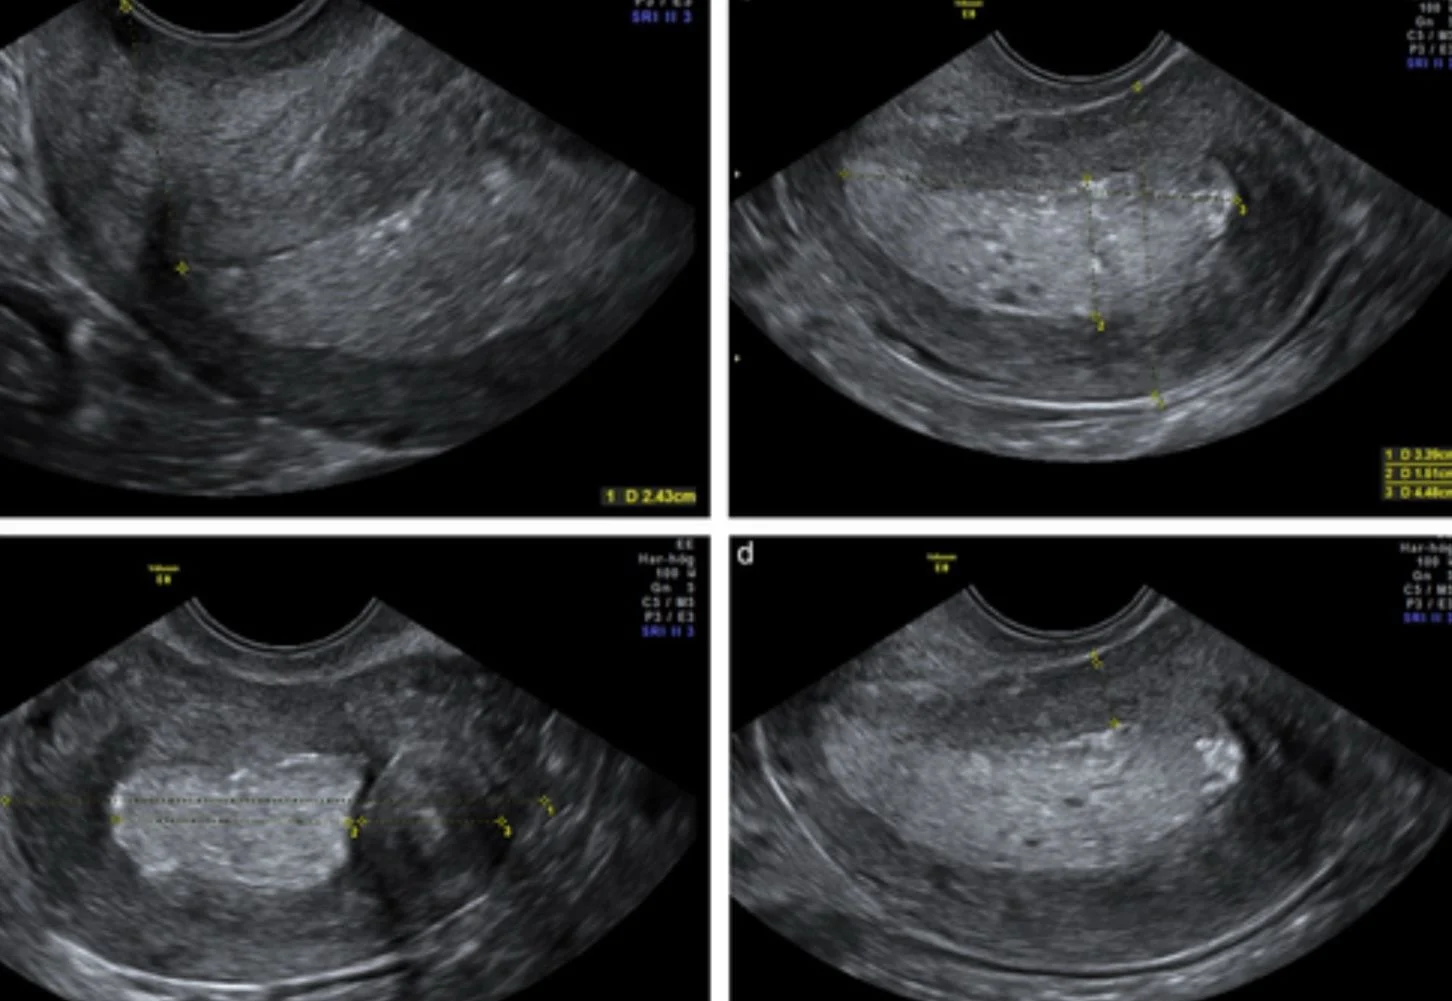

2. Sonographic Hallmarks

When evaluating the uterus for malignancy, sonographers and radiologists look for several specific “red flags.”

- Echogenicity: The endometrium often appears heterogeneous, thickened, and “dirty” or complex compared to the surrounding tissue.

- The Subendometrial Halo: A healthy uterus has a thin, hypoechoic (dark) zone between the endometrium and myocardium. Loss or blurring of this ‘halo’ suggests myometrial invasion.

- Fluid Collections: While simple fluid (hydrometra) can be benign, fluid containing echoes (hemometra or pyometra) in a postmenopausal patient is suspicious.